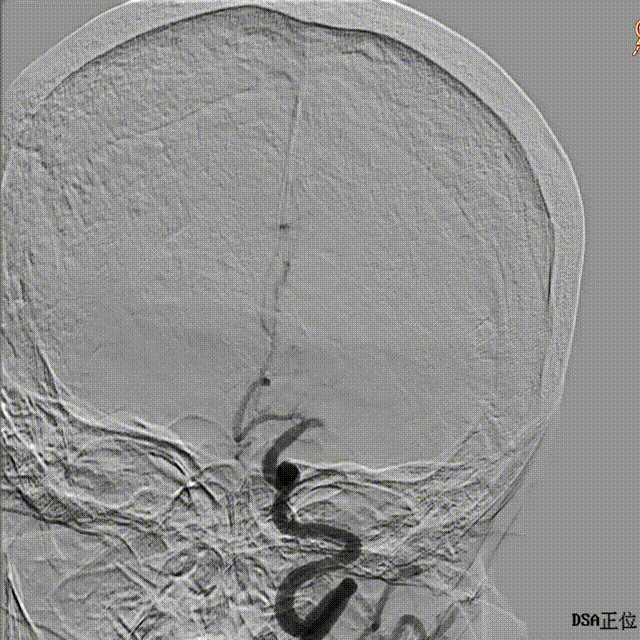

正侧位造影。

正位

侧位